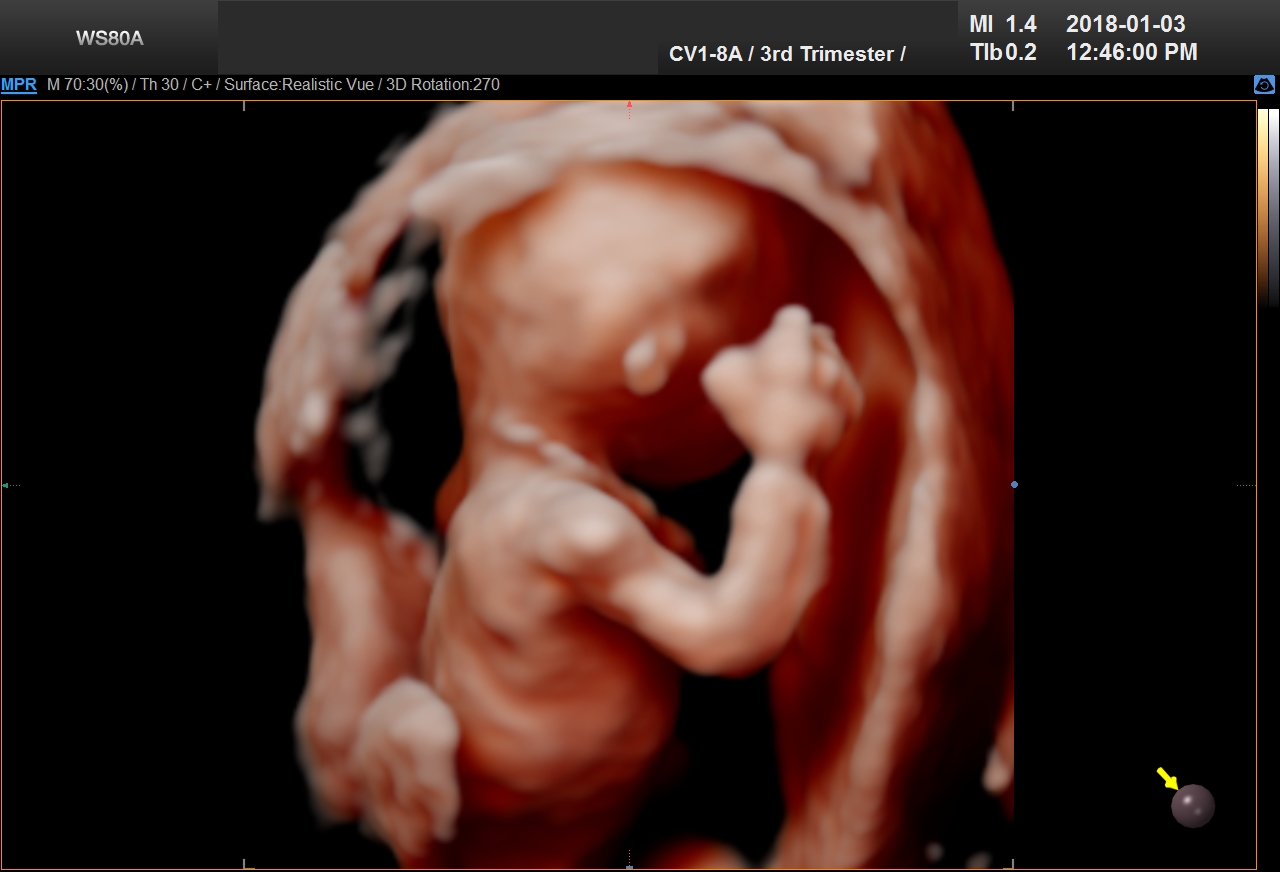

5D Ultrasound is the newest development in pregnancy imaging and it is patented by Samsung. It captures and combines high definition volume data to create automated images with amazing color and clarity. The bond between a new baby and the family gets even stronger when the family can view realistic pictures of baby in a 5D ultrasound.

UC Baby’s Latest 5D Ultrasound Service Offering

UC Baby Calgary is the first facility which brought cutting edge 5D technology to Canada. This cutting edge new ultrasound machine provides realistic pictures of the baby using the most advanced features of ultrasound imaging. We are offering high-definition 5D ultrasound technology to create unforgettable memories without extra cost. This new ultrasound technology allows families to bond stronger to the baby, with clear views of baby’s face and movements. With 5D technology, it is even possible to notice the dimples when baby smiles!

The best time to have a 5D ultrasound is between 24-32 weeks of pregnancy. Our experienced and professionally trained staff are there to amaze the mothers and their families. We also offer free online accounts for captured 2D, 3D, 4D and 5D images / videos in addition to free live broadcast of the whole ultrasound session. This is the fastest and easiest way to share baby’s first pictures and videos with friends and family instantly.